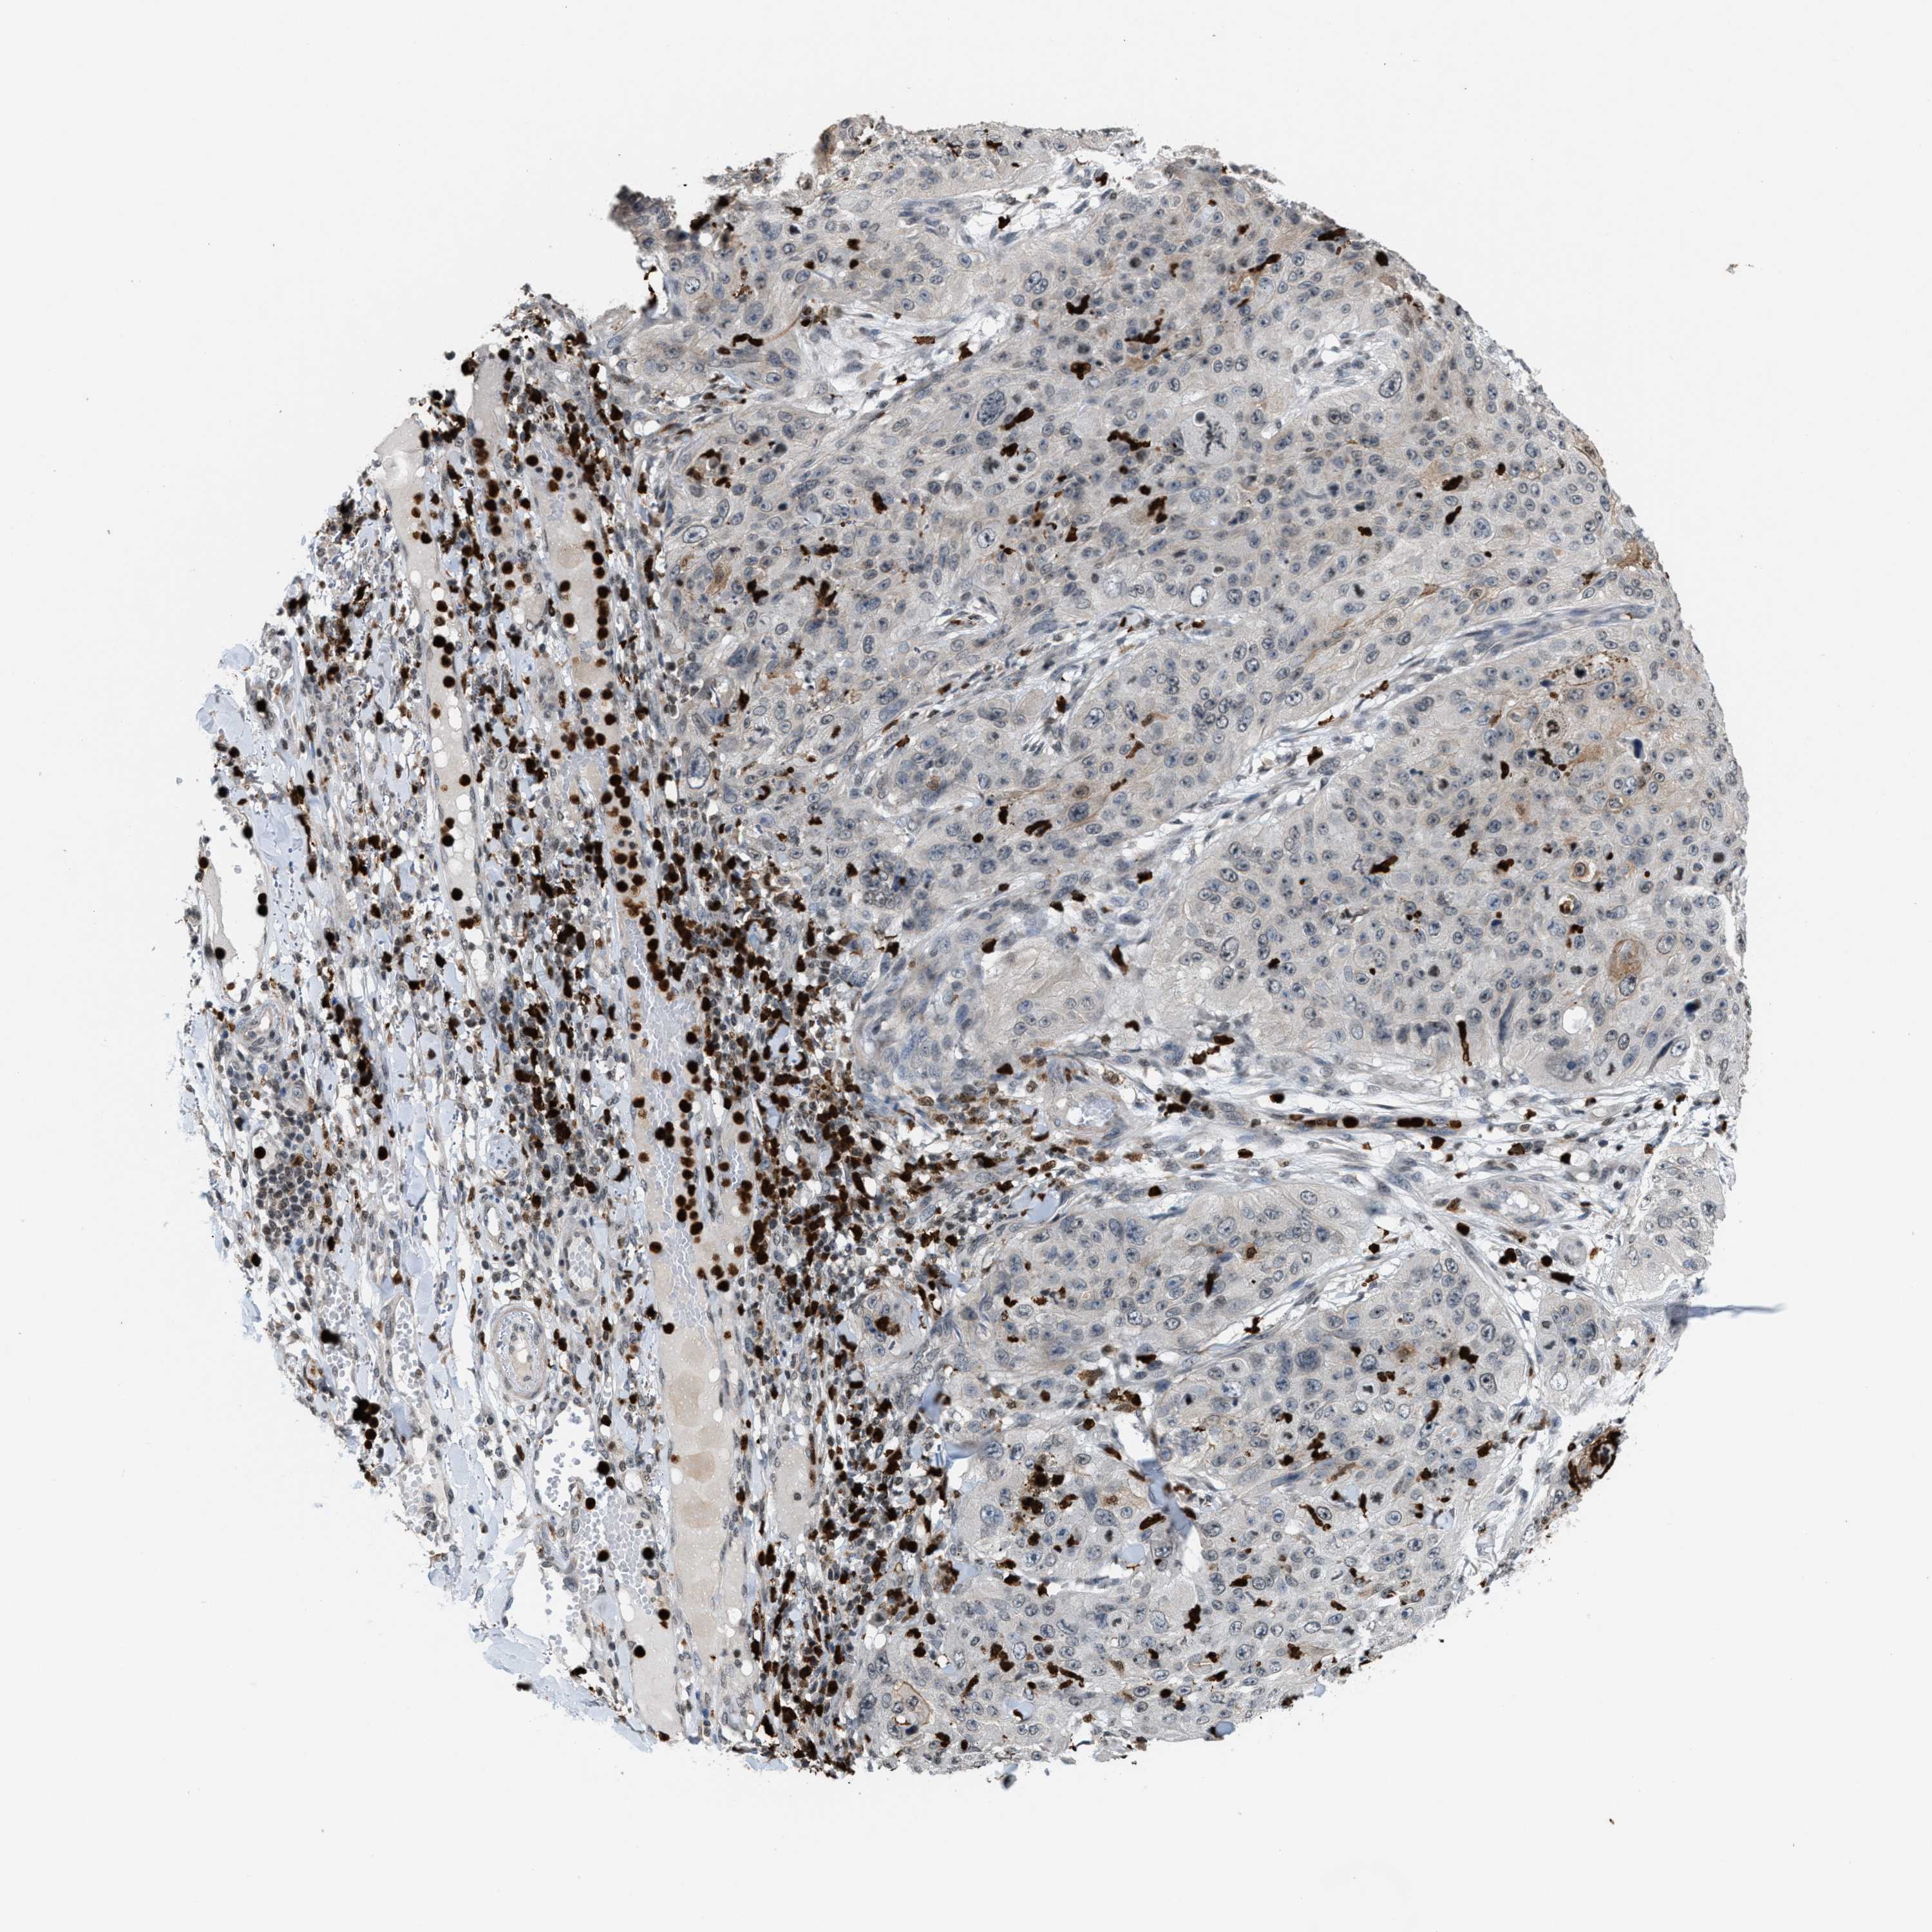

SKIN CANCER - Protein expressioni

A mouse-over function shows sample information and annotation data. Click on an image to view it in a full screen mode. Samples can be filtered based on level of antibody staining by selecting one or several of the following categories: high, medium, low and not detected. The assay and annotation is described here.

Each image is clickable and will lead to virtual microscopy that enables deeper exploration of all samples and also displays staining intensity scores, fraction scores and subcellular localization as well as patient and tissue information for each sample.

Antibody HPA031079

Staining

High

Medium

Low

Not detected

Intensity

Strong

Moderate

Weak

Negative

Quantity

>75%

75%-25%

<25%

None

Location

Nuclear

Cytoplasmic/membranous

Cytoplasmic/membranous,nuclear

Basal cell carcinoma

Adnexal tumor, benign